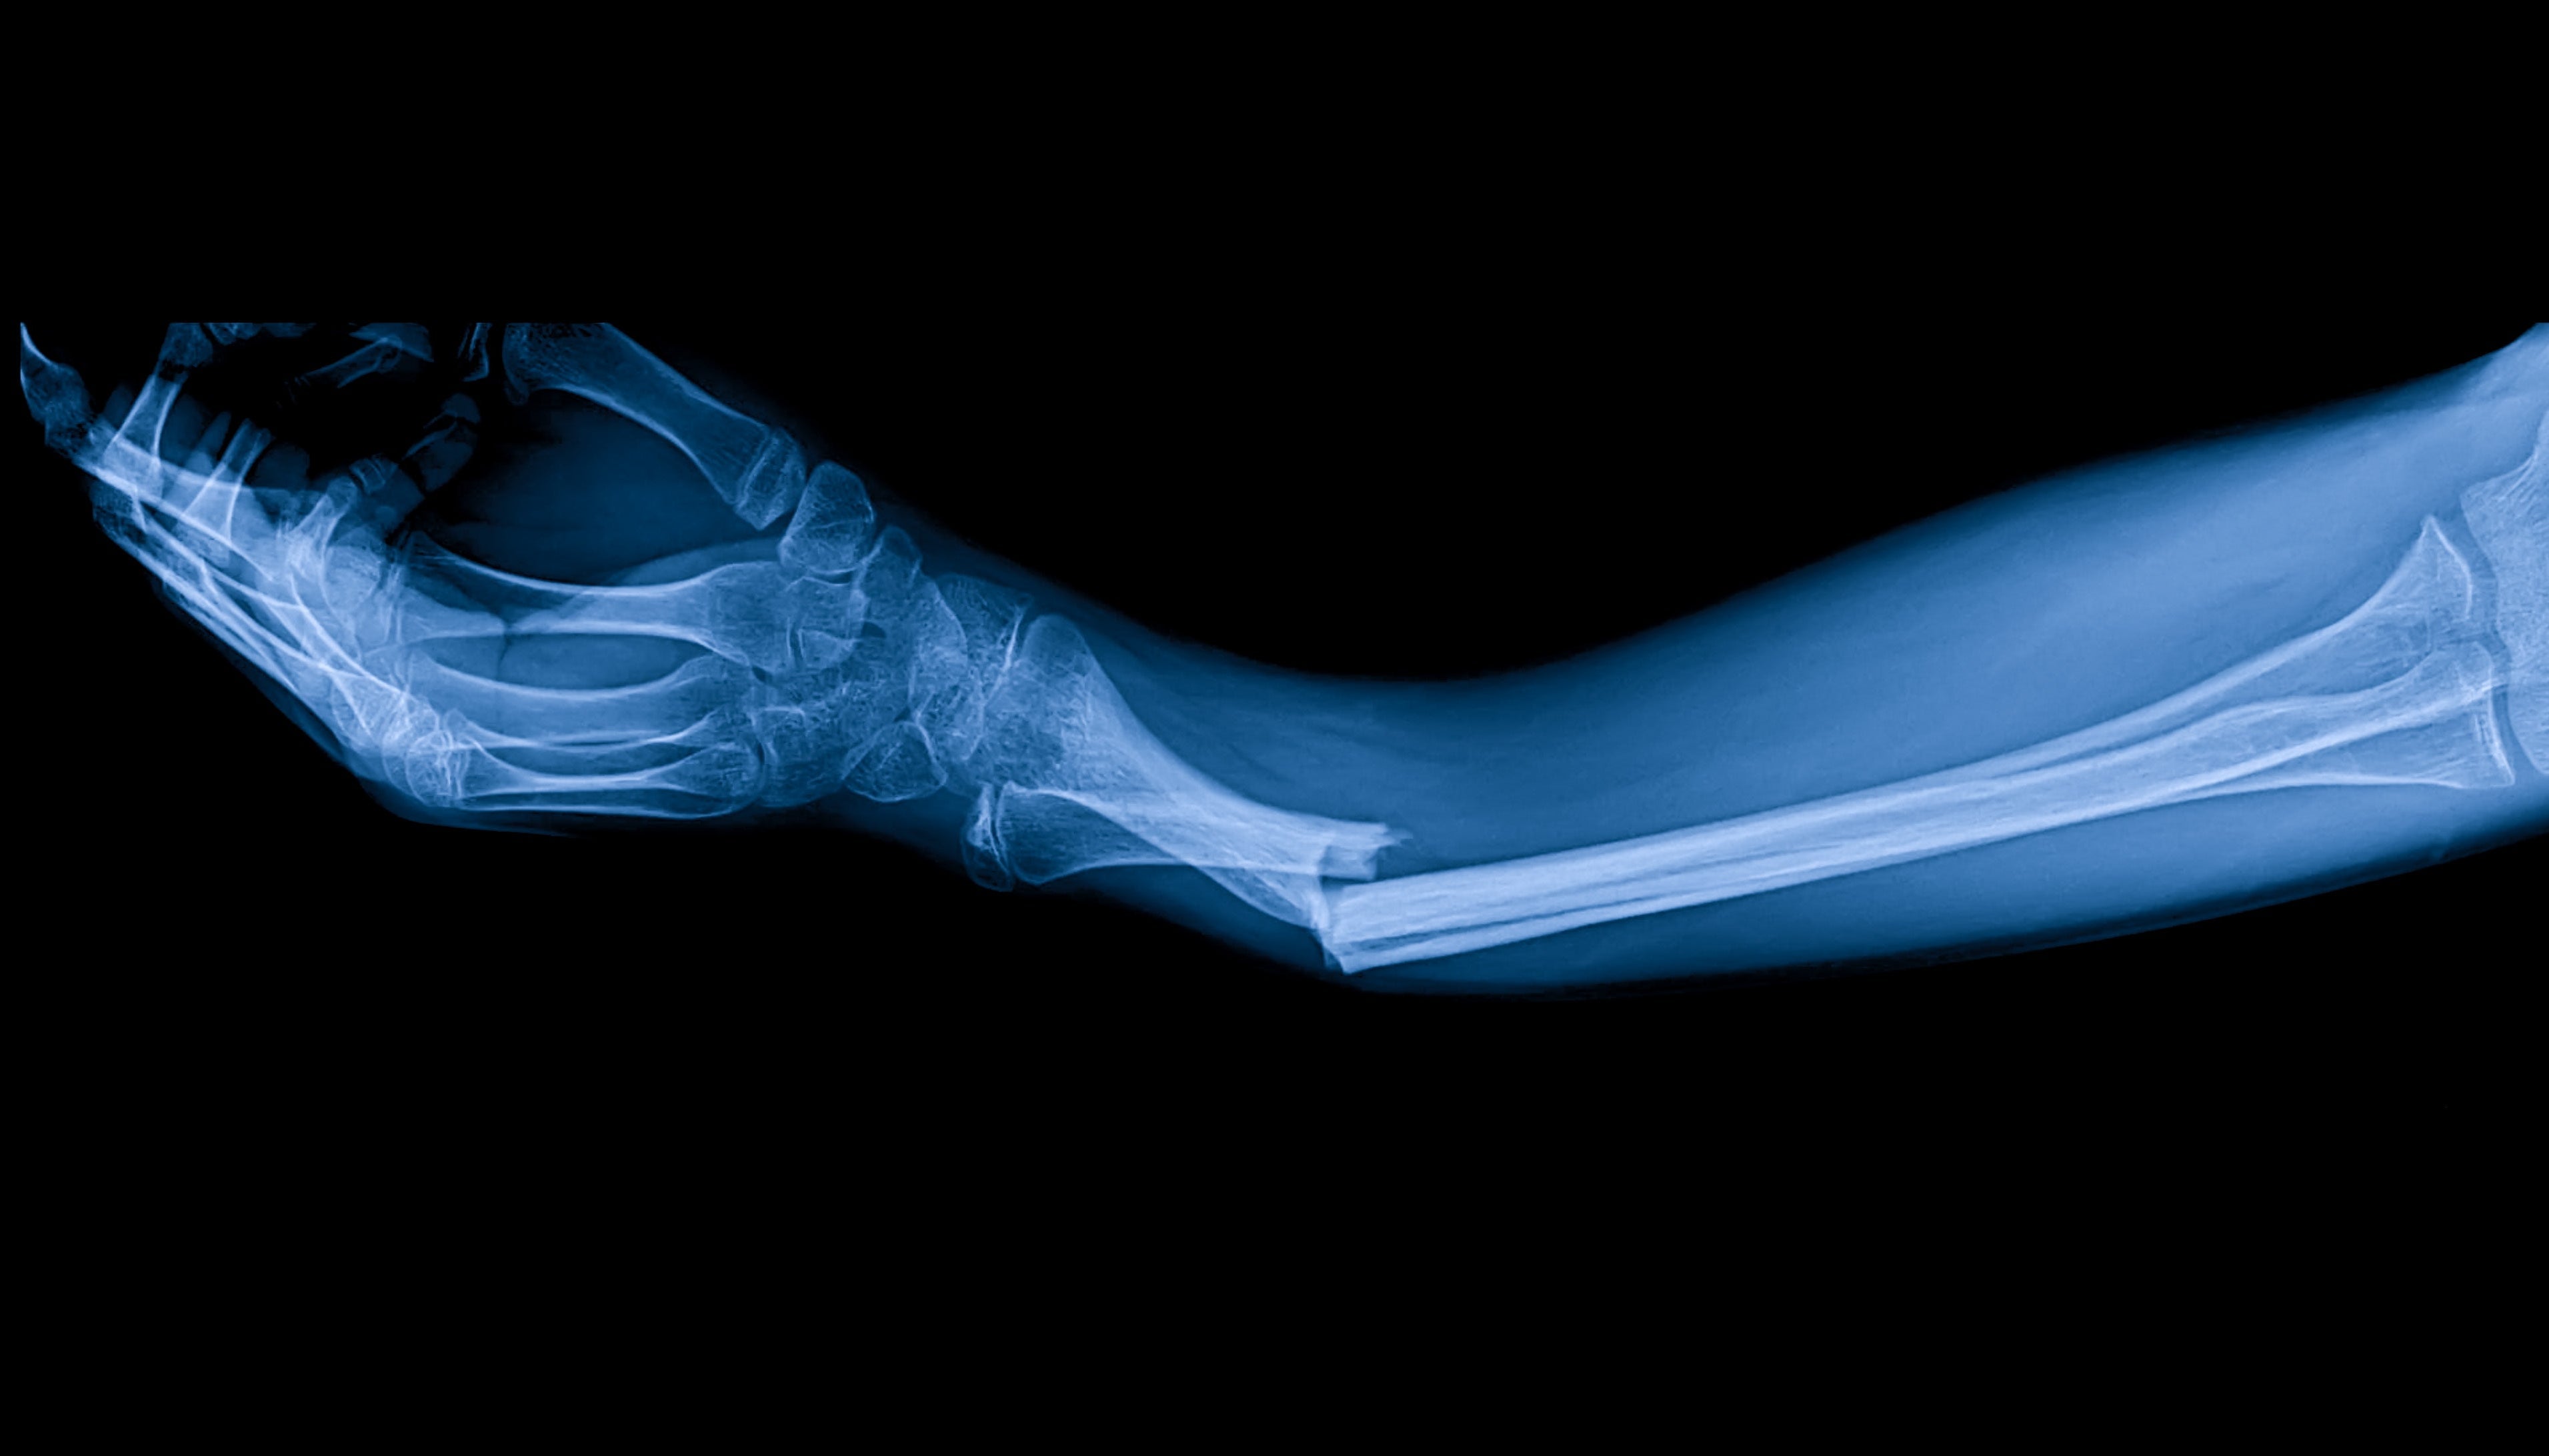

Knochenbrüche können die Folge von Unfällen, Stürzen oder Sportverletzungen sein und erfordern je nach Schwere und Lage des Bruchs eine lange Erholungszeit. Zu den herkömmlichen Knochenheilungsmethoden gehören die Ruhigstellung mit Gips oder Schienen und manchmal auch chirurgische Eingriffe. Die PEMF-Therapie ergänzt diese Methoden, indem sie die zelluläre Reparatur und das Knochenwachstum auf molekularer Ebene stimuliert.